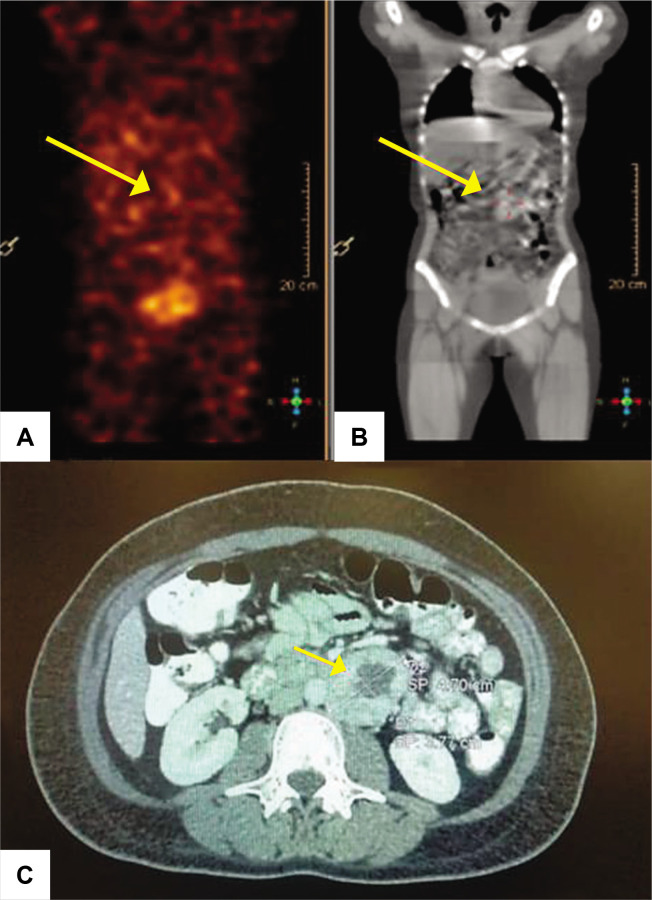

Due to its rarity, pheochromocytoma or paraganglioma (PPGL) in pregnancy is often not timely diagnosed, thus resulting in high materno-fetal complications. We report a 28-year-old female who presented with paroxysmal symptoms and severe hypertension during early pregnancy. Biochemical confirmatory tests and localization imaging were delayed due to multiple factors. She suffered from two pregnancy losses before she had resection of the paraganglioma.